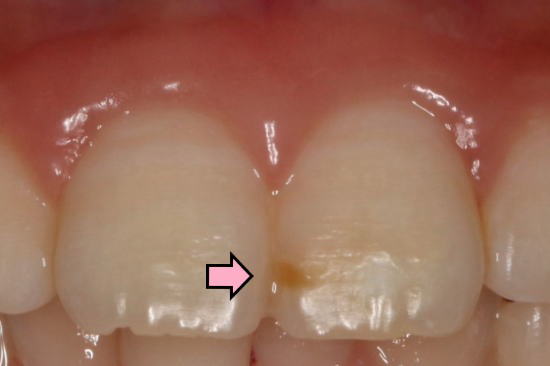

| 初診時の口腔内写真:2015年08月26日 砂糖が入ったスポーツドリンクの常用で全体の歯がむし歯になりかけ 砂糖入りのスポーツドリンクをやめて、毎日フッ素洗口をするよう勧める。 |

前歯の拡大: 矢印の所がむし歯(白濁)が進行している。 |